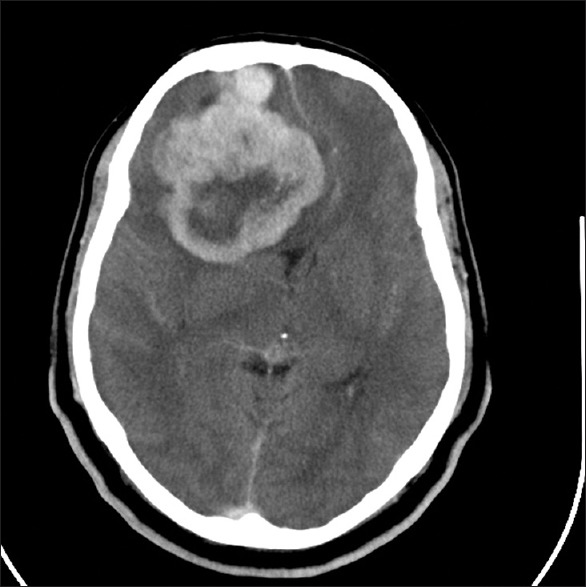

一名43岁的已婚男性患者来到医院的OPD精神病院进行咨询。在过去的两个月里,病人抱怨一天中大部分时间都很难过。他也开始比平时少说话,并且会保持安静。这伴随着睡眠和食欲下降。患者看了私人精神病医生,被诊断为没有精神病特征的中度抑郁障碍(根据ICD-10,F-32.1)。他被开了50毫克/天的去文拉法辛片。患者病情未见好转,来到帕蒂拉RH就诊。患者现在也有健忘和头痛的主诉以及先前的抑郁症状。没有头部创伤史或任何局灶性神经功能缺损。没有任何精神疾病的家族史。一般的身体检查和神经系统检查都没有异常。精神状态检查,他的情绪低落,近期记忆受损。患者被告知CECT头部显示一个较大的轴外高密度肿块,大小约为。右前区7 cm×6.3 cm。病灶呈不均匀强化,有坏死区,提示右侧额脑膜瘤恶变(图2)。该病例被转到神经外科做进一步处理。

图2